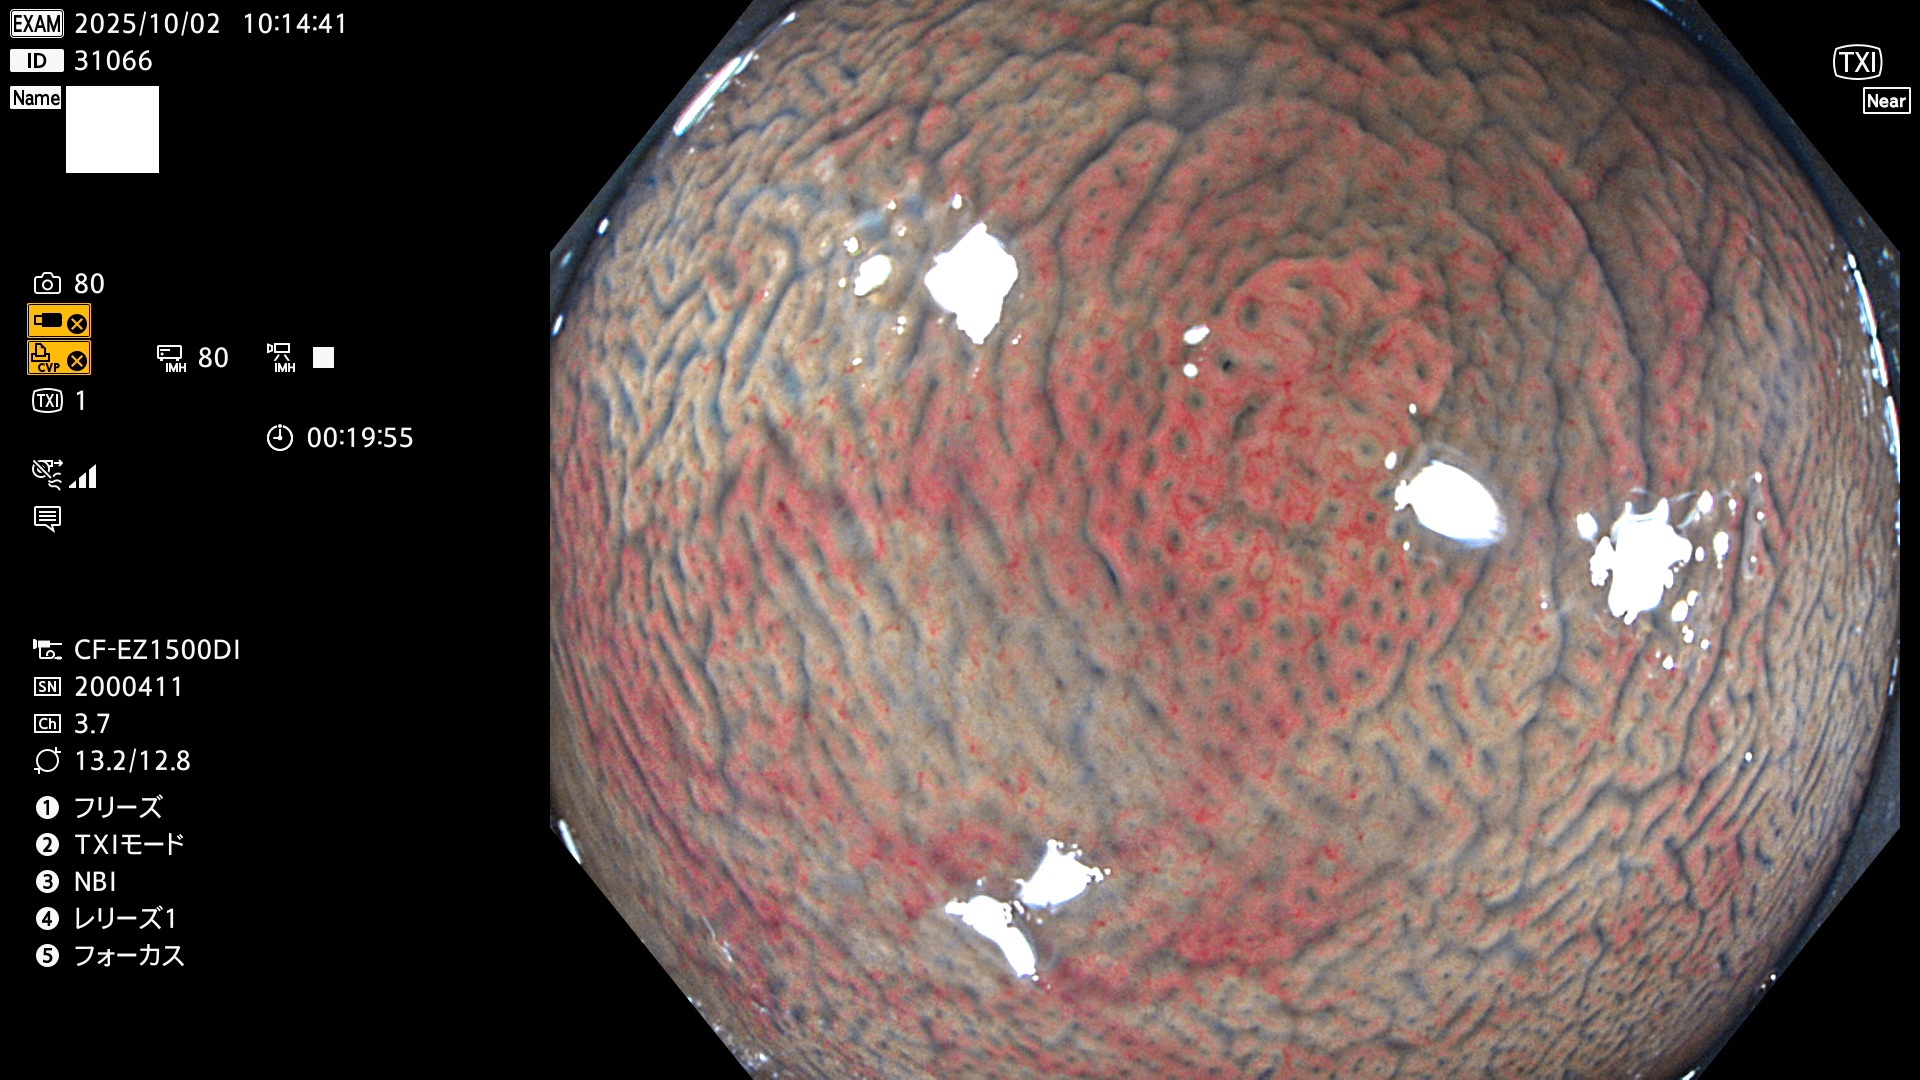

完全に平坦な物をUb、陥凹している物をUcと呼びます。Ubは認識が困難で、Ucはびらん(炎症)と紛らわしいために見落とされやすく、「内視鏡後・大腸癌」の原因になります。

専門的)Uc=De Novo癌? 内視鏡の解像度が低かった時代、このような説もありました。しかし今日の高精度内視鏡では良性の微小なUc型腺腫(APC遺伝子異常の腺腫)が日常的に見つかります。Ucこそが多段階発癌(Adenoma-Carcinoma Sequence)のMain Routeです。

毎週の検査(木・金・土・日)に発見されたUbとUc型・腺腫を、その週の日曜の夜にUPし1週間、提示します。

2025年10月2日〜10月5日の4日間(40件)9個 (Uc_ADR=9個/40人=23%)